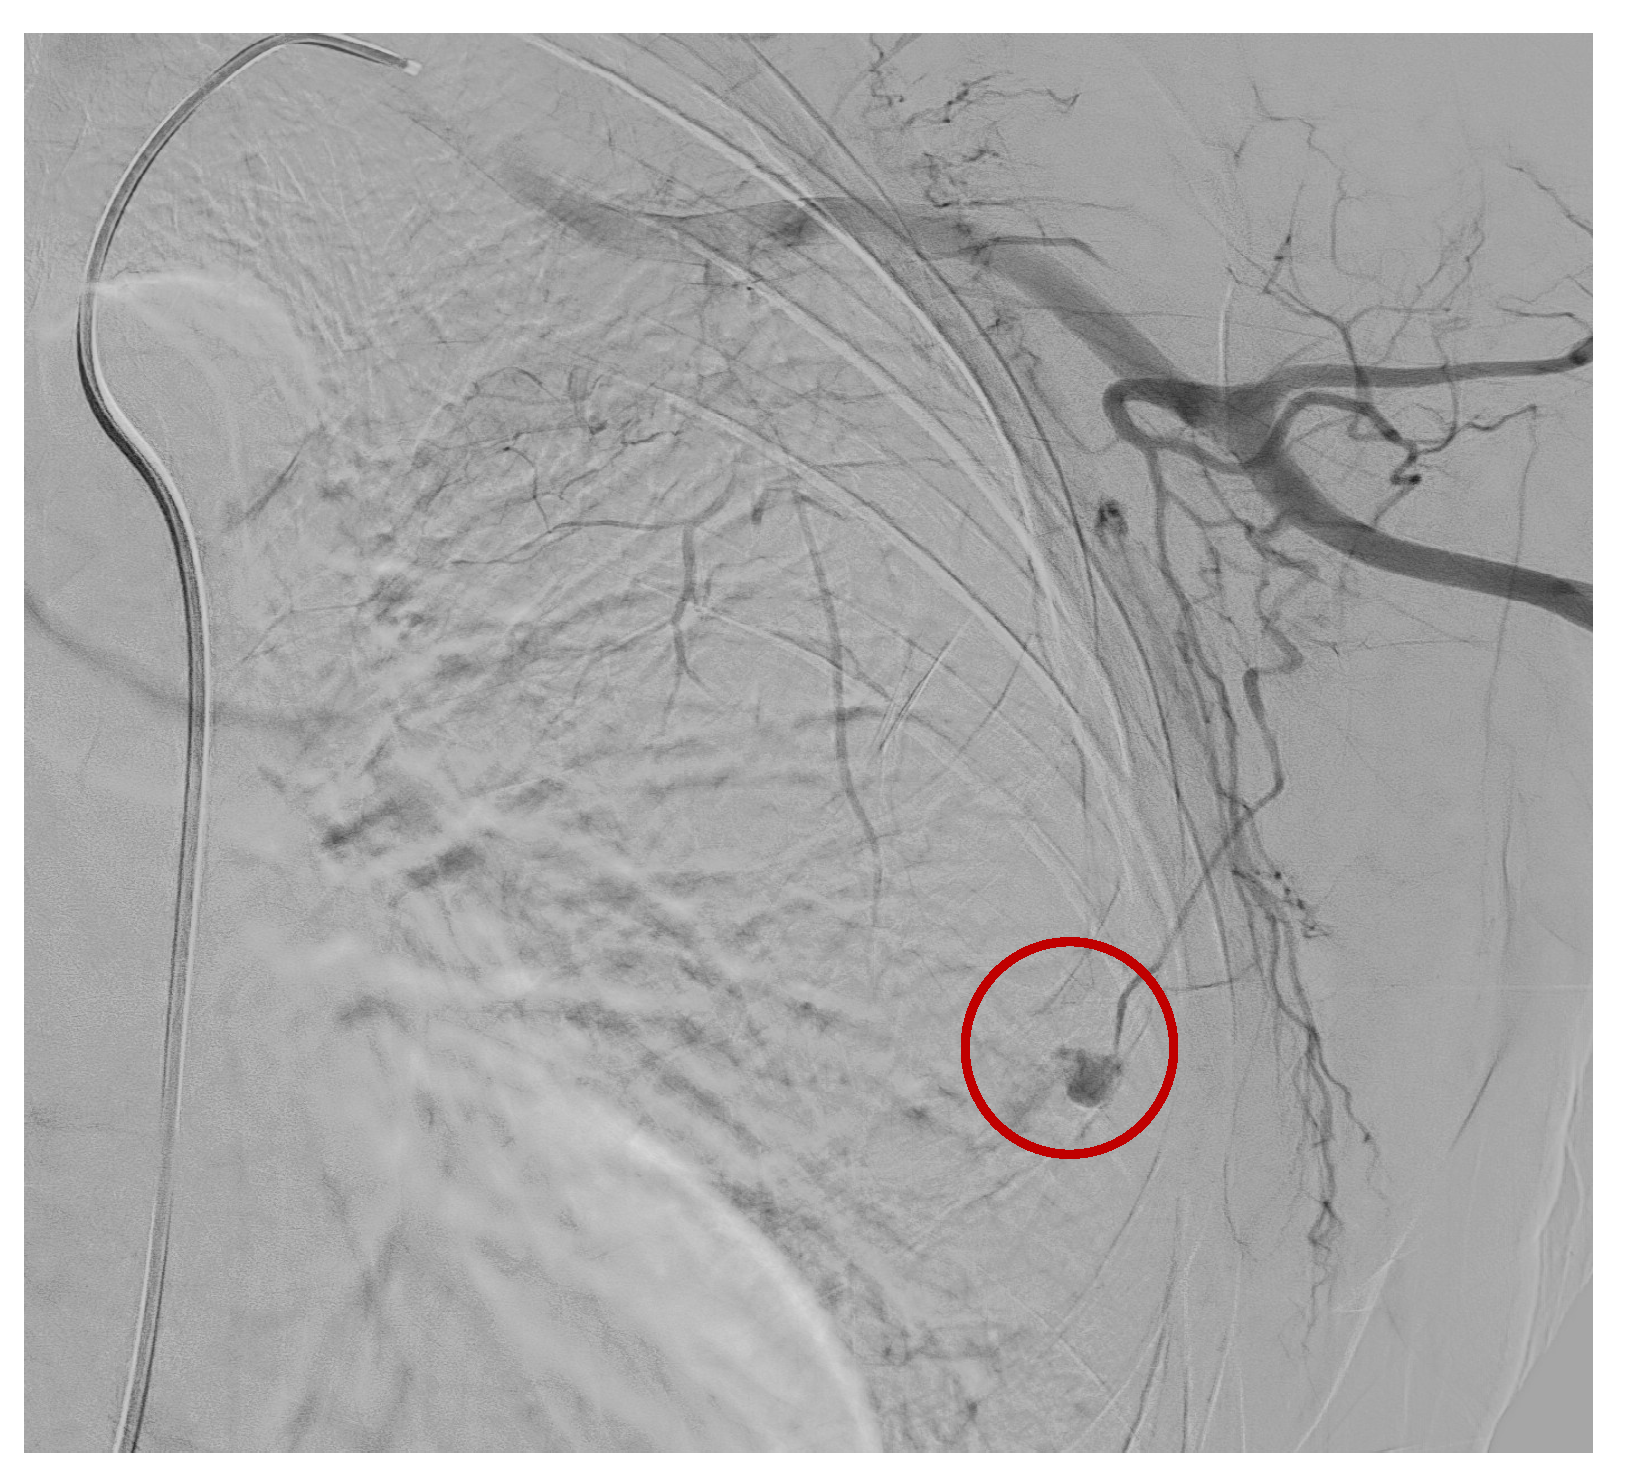

A preliminary angiographic examination documented the spread of a contrast medium by the distal branch of the lateral thoracic artery, which was embolized by releasing two metal coils (2 mm × 2 cm and 2 mm × 4 cm) (Figure 3 and Figure 4).

Figure 4.

Blood spread by the distal branch of the lateral thoracic artery. (Red circle).

The final controls confirmed the successful outcome of the procedure with the correct occlusion of the treated vessel without images compatible with active bleeding.